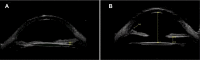

Results: A 69-year-old patient complained of decreased visual acuity 11 months after undergoing phacoemulsification. She was found to have a secondary myopization. Anterior segment ultrabiomicroscopy confirmed the diagnosis of capsular block syndrome. The patient underwent neodymium-doped yttrium aluminum garnet (Nd:YAG) laser posterior capsulotomy, which resulted in complete resolution of her symptoms.